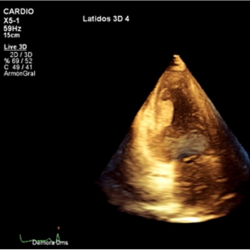

Figure 3.

3D-transthoracic echocardiogram. Apical two-chamber view. Mass attached to the left ventricular inferior wall.